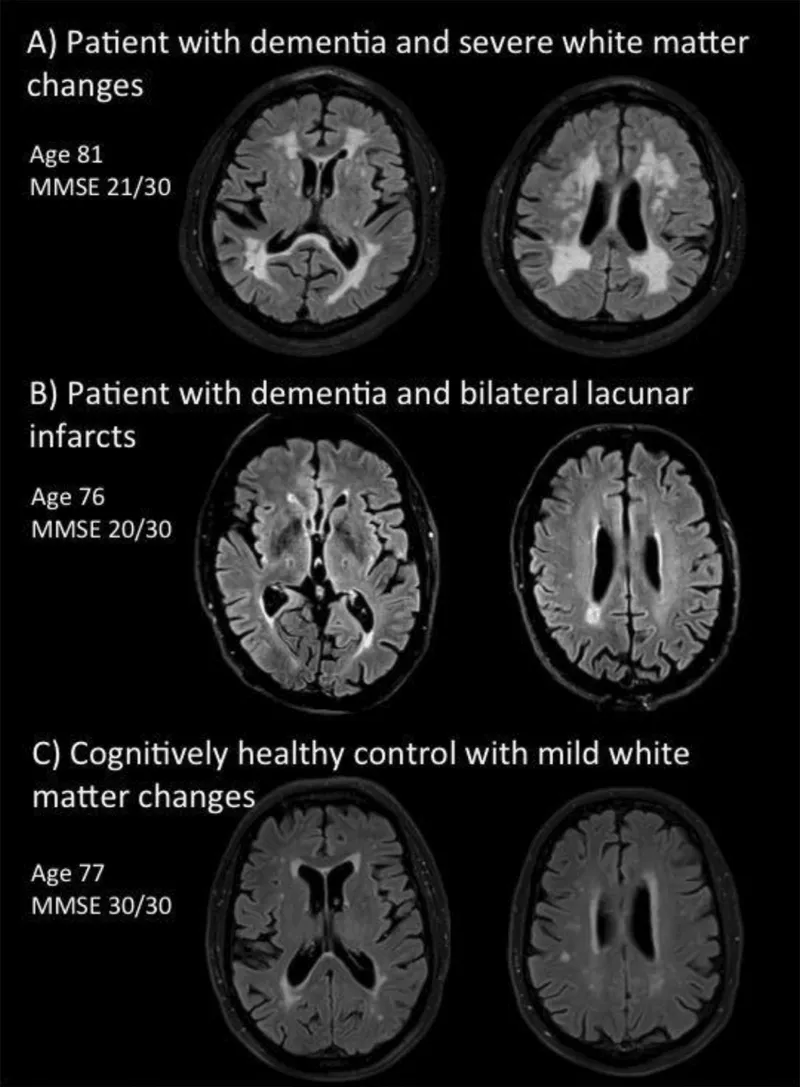

Vascular Dementia - Brain Blood Block

Caused by cerebrovascular disease (multi-infarct, small vessel disease).

- Diagnosis:

- Clinical assessment.

- Hachinski Ischemic Score (> 7 suggests VaD).

- Neuroimaging: infarcts, white matter lesions.

⭐ Stepwise deterioration with focal neurological deficits is characteristic of multi-infarct dementia (a type of Vascular Dementia).